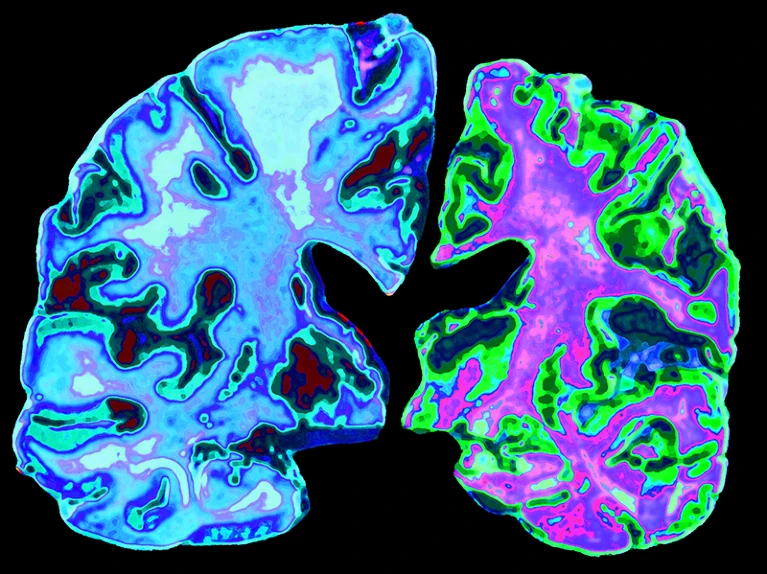

70세 정상인의 뇌(왼쪽)와 알츠하이머병을 앓고 있는 70세 환자의 뇌(오른쪽) 사진 비교

출처 : Nature, ‘Transmissible’ Alzheimer’s theory gains traction, 2018.12.